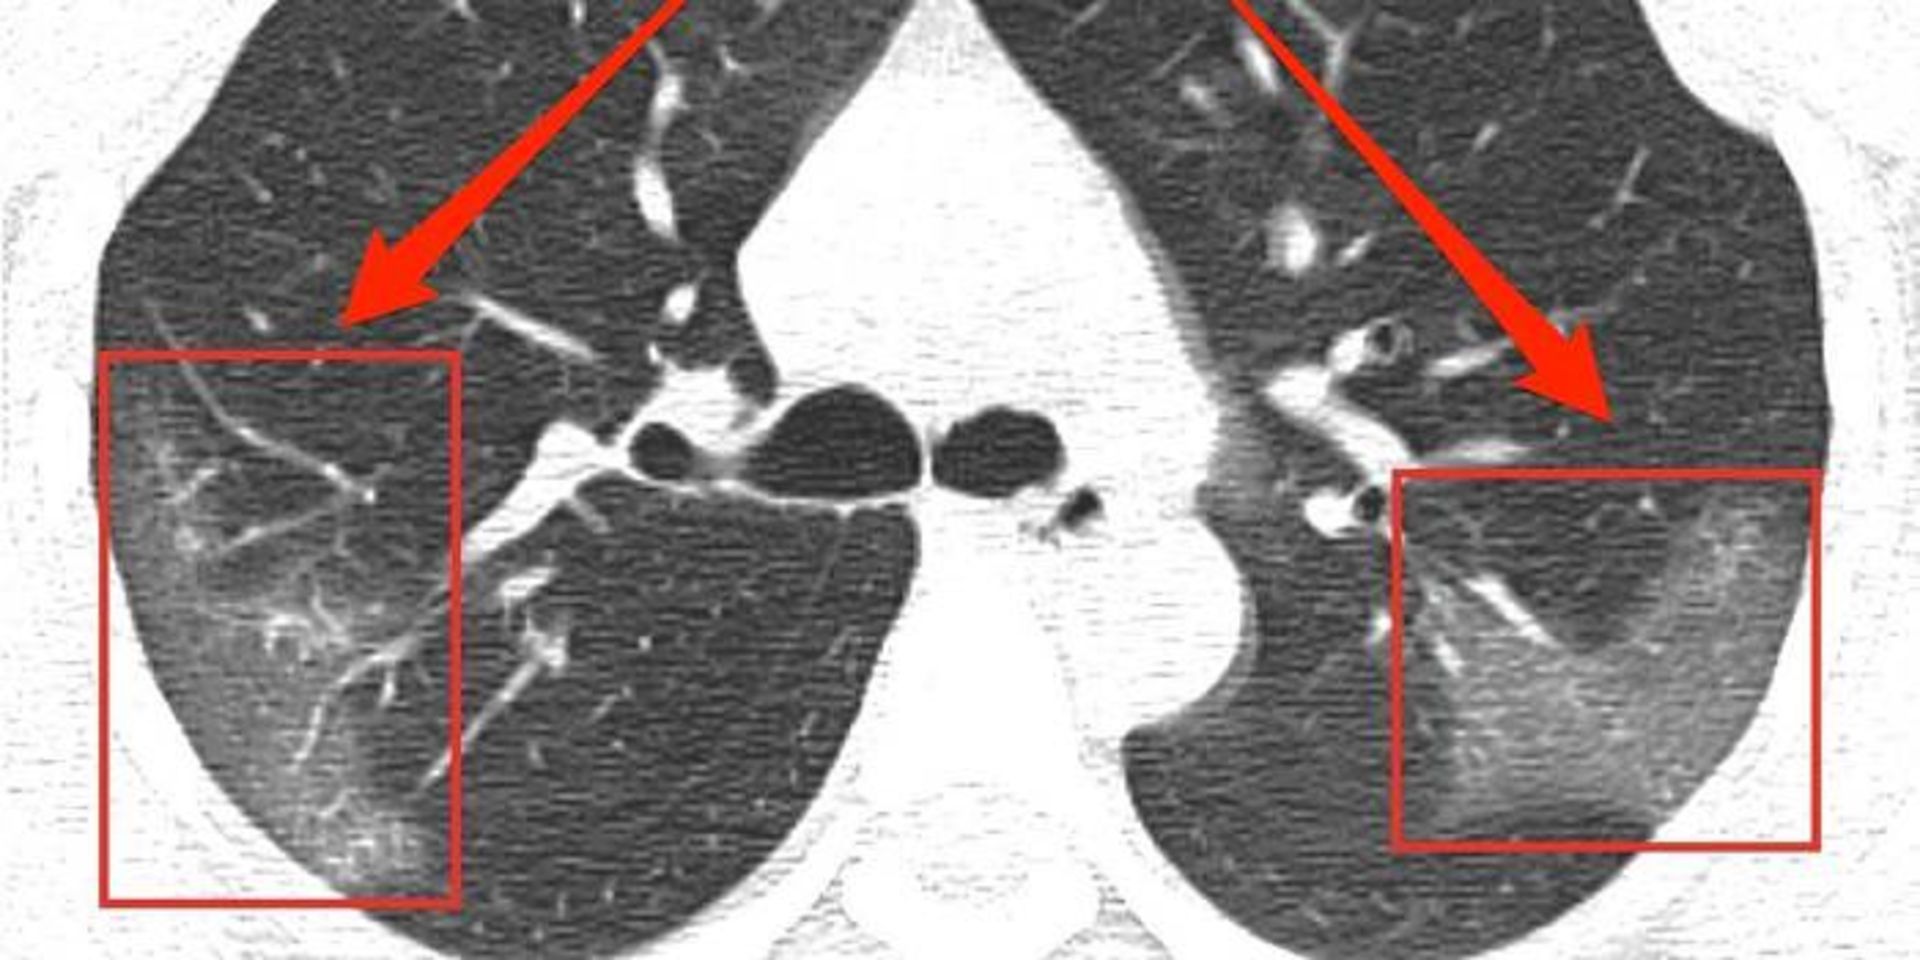

پزشکان پس از اسکن ریه‌های بیماران نشانه‌هایی از واردشدن آسیب به این عضو را مشاهده کردند. این اندازه نمونه برای اعلام این موضوع کم است که کووید ۱۹ لزوما موجب آسیب بلندمدت می‌شود؛ اما باید برای پزشکان نشانه‌ای هشداردهنده درباره‌ی ضرورت مراقبت از عوارض احتمالی باشد.